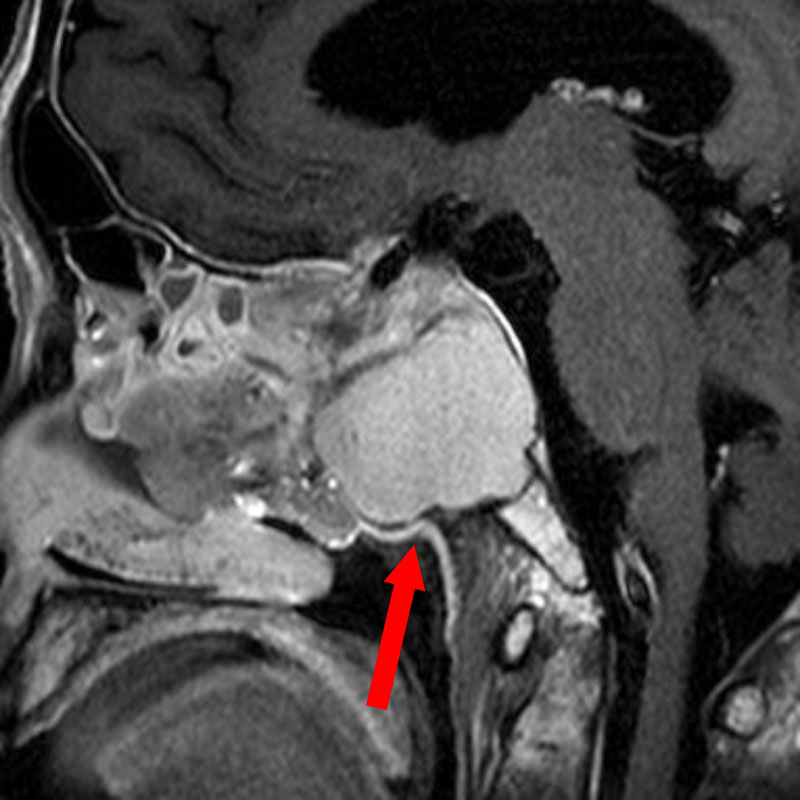

670

'25年9月

70代

小脳橋角部髄膜腫

頭蓋内腫瘍摘出術

No.’25_72 手術前1

No.’25_72 手術前2